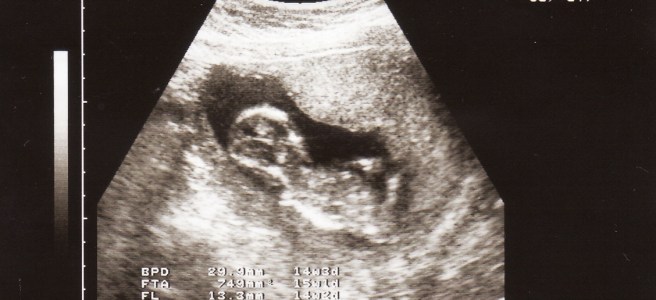

hari ni mama, abah, darwisy and danish macam biasa bersarapan di luar. cuma kali ni tak makan di restoran mamak, tapi di restoran melayu di sekitar bangi. tiap2 minggu makan roti canai je bosan gak 🙂 lepas je sarapan, kami meneruskan perjalan ke kajang. bukan tujuan berjalan-jalan tapi nak pegi klinik pakar wanita untuk scan … Teruskan membaca baby girl? InsyaAllah…

mari menaip lagi 🙂 syukur Alhamdulillah, pada tahun 2010 yang lepas kami telah dikejutkan dengan beberapa berita gembira. antaranya... tak lama lagi kami akan menerima seorang lagi ahli keluarga yang baru 🙂 Insya Allah... my wife is now a teacher 🙂 nak dijadikan cerita... pada satu malam tu, aku dan famili pegi kuar jalan2 sambil … Teruskan membaca the 3rd